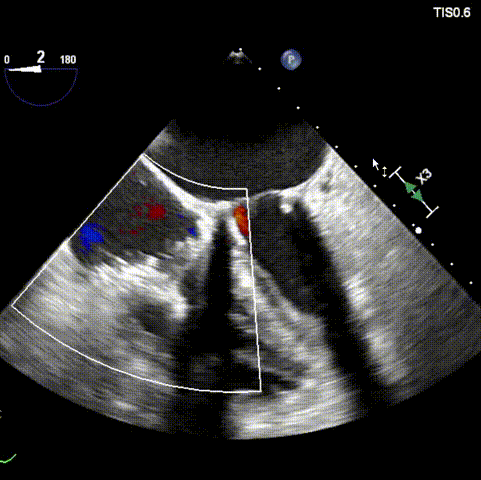

本次接受治疗的患者是一名74岁的女性,14年前因风湿性心脏病行二尖瓣生物瓣植入术,合并房颤。近3年来反复因腹胀、纳差、下肢水肿入院,药物治疗欠佳。心脏超声显示三尖瓣极重度反流(有效反流口面积:0.76cm²,反流容积:79ml),继发性右房室增大及上、下腔静脉增宽(右房上下径*左右径:52*41mm,右室左右径:46mm,下腔静脉:29mm),右室收缩功能正常,肺动脉收缩压 43mmHg,左心室射血分数73% 。患者既往开胸手术史,术前评估STS 评分为7.02分,CRS 9分,无法接受体外循环下三尖瓣外科手术。面对这一传统治疗无法解决的困境,葛均波院士及其团队周达新教授、潘文志教授、张源博士、陈莎莎博士及心超室的潘翠珍教授、李伟教授经过讨论决定,采用创新的Lux-Valve Plus系统为患者进行经血管三尖瓣置换。

手术在患者全麻状态下进行,采用经右侧颈静脉作为入路,将装载有人工瓣膜的输送器缓慢推送至右心房;并在经食道超声和DSA的引导下小心调整输送器角度,将输送器送入右心室;逐步释放瓣膜锚定装置和盘片,调整瓣膜位置后,锚定瓣膜完成植入。术后右房压明显下降,从术前的25/10(16) mmHg降至术后即刻的12/7(10) mmHg,术后超声提示人工三尖瓣同轴性良好,固定牢固,无反流及瓣周漏手术室即刻拔除气管插管。